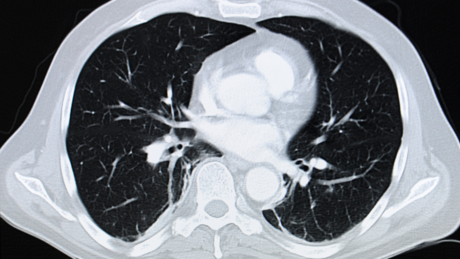

Kardio-CT

Der Klinik für Innere Medizin, Herz- und Kreislauferkrankungen steht ein für die Herz- und Gefäßbildgebung geeigneter Computertomograf der Firma Siemens zur Verfügung. Es handelt sich um ein sogenanntes 64-Zeilen-CT.

Das Gerät wird unter dem Dach der Klinik für Diagnostische Radiologie betrieben, die Herz-Untersuchungen werden gemeinsam von Kardiologen und Radiologen durchgeführt.

In weniger als 500 ms, also ungefähr der Zeit eines halben Herzschlages, dreht sich das Gerät einmal komplett um den ganzen Körper. Dabei dient der Röntgenstrahl unter Einsatz eines besonderen Detektorsystems der simultanen Erfassung mehrerer Schichten pro Umdrehung ("Mehrschicht-CT", "MSCT" oder "Multidetektor-CT", "MDCT"). Moderne Mehrzeilendetektoren ermöglichen sehr dünne Schichten (< 1 mm), mit denen innerhalb weniger Sekunden ein ausreichend großer Bereich des Körpers abgebildet werden kann. Mit diesem Verfahren können die Koronararterien in hervorragender Qualität abgebildet werden.

Aufgrund der kurzen Untersuchungszeit reduziert sich die notwendige Strahlenexposition oft um ein Vielfaches. Es ist besonders wichtig, dass eine CT-Koronarangiographie in ein sinnvolles diagnostisches und therapeutisches Gesamtkonzept eingebunden wird.

Das Herz-CT ist nur so gut, wie die Frage, die an diese Methode gestellt wird. Wir wenden den für den Patienten entscheidenden Fragen („Was bedeutet der Befund für mich?“ und „Welche Konsequenz hat dieser Befund?“) deshalb besondere Aufmerksamkeit zu. Nach der Untersuchung werden deshalb von einem Kardiologen mit Ihnen gemeinsam der Befund und seine Konsequenzen ausführlich erläutert.